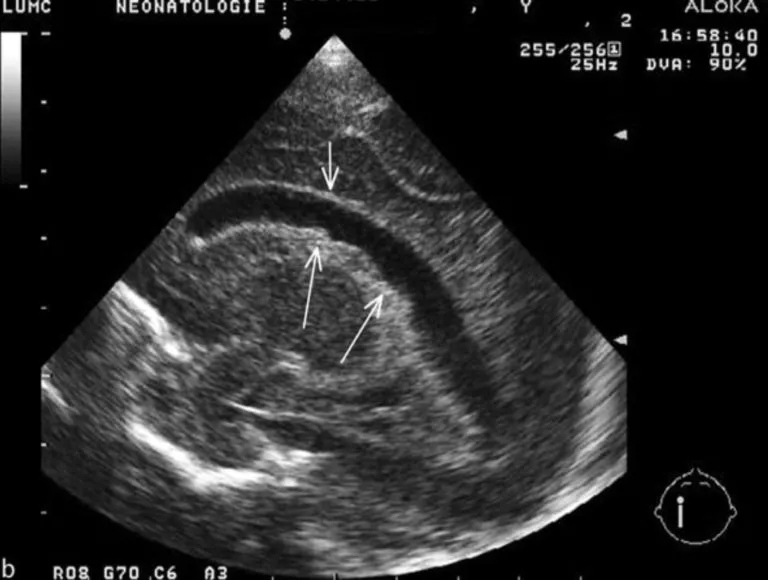

Po co u dzieci urodzonych przedwcześnie robi się USG główki (USG przezciemiączkowe)?

1:02 min.

Po co u wcześniaków robi się echo serca? Co to jest przewód tętniczy?

1:47 min.